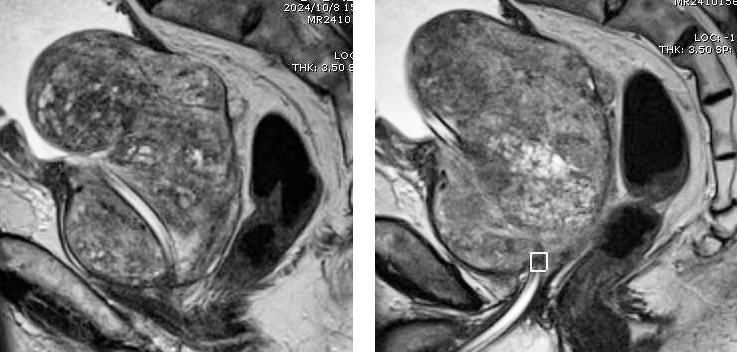

此次,患者因不愿長期留置尿管,要求行手術(shù)治療。前列腺MRI檢查示前列腺巨大,大小為351克,且合并膀胱多發(fā)結(jié)石。一般前列腺肥大手術(shù)患者大小多在20-100克,超過200克的病例較為罕見,此例患者臨床極為罕見,為我院開展前列腺手術(shù)最大體積前列腺。一般超大體積前列腺多采取開刀手術(shù),可縮短手術(shù)時間,但開刀手術(shù)創(chuàng)傷大,術(shù)中術(shù)后出血較多,患者術(shù)后恢復(fù)慢,痛苦大,且存在膀胱漏尿,切口裂開等并發(fā)癥。